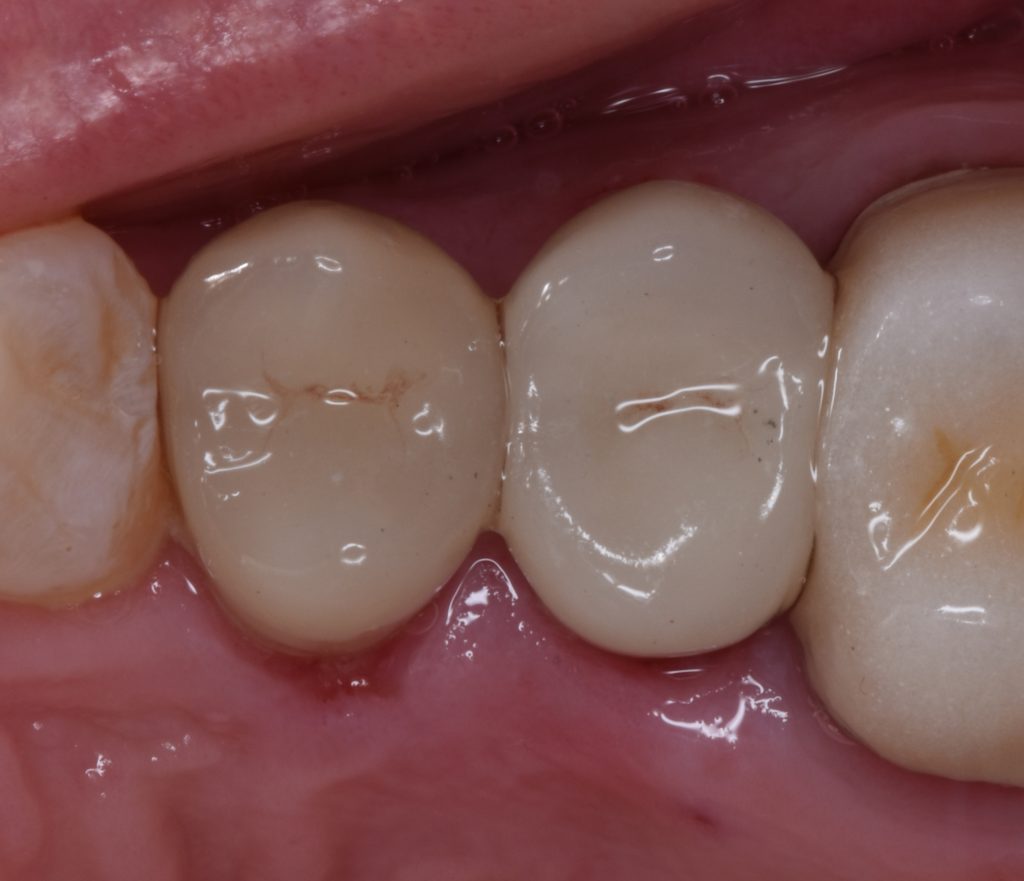

Upper right first and second premolars

Were badly decayed

Upon examination